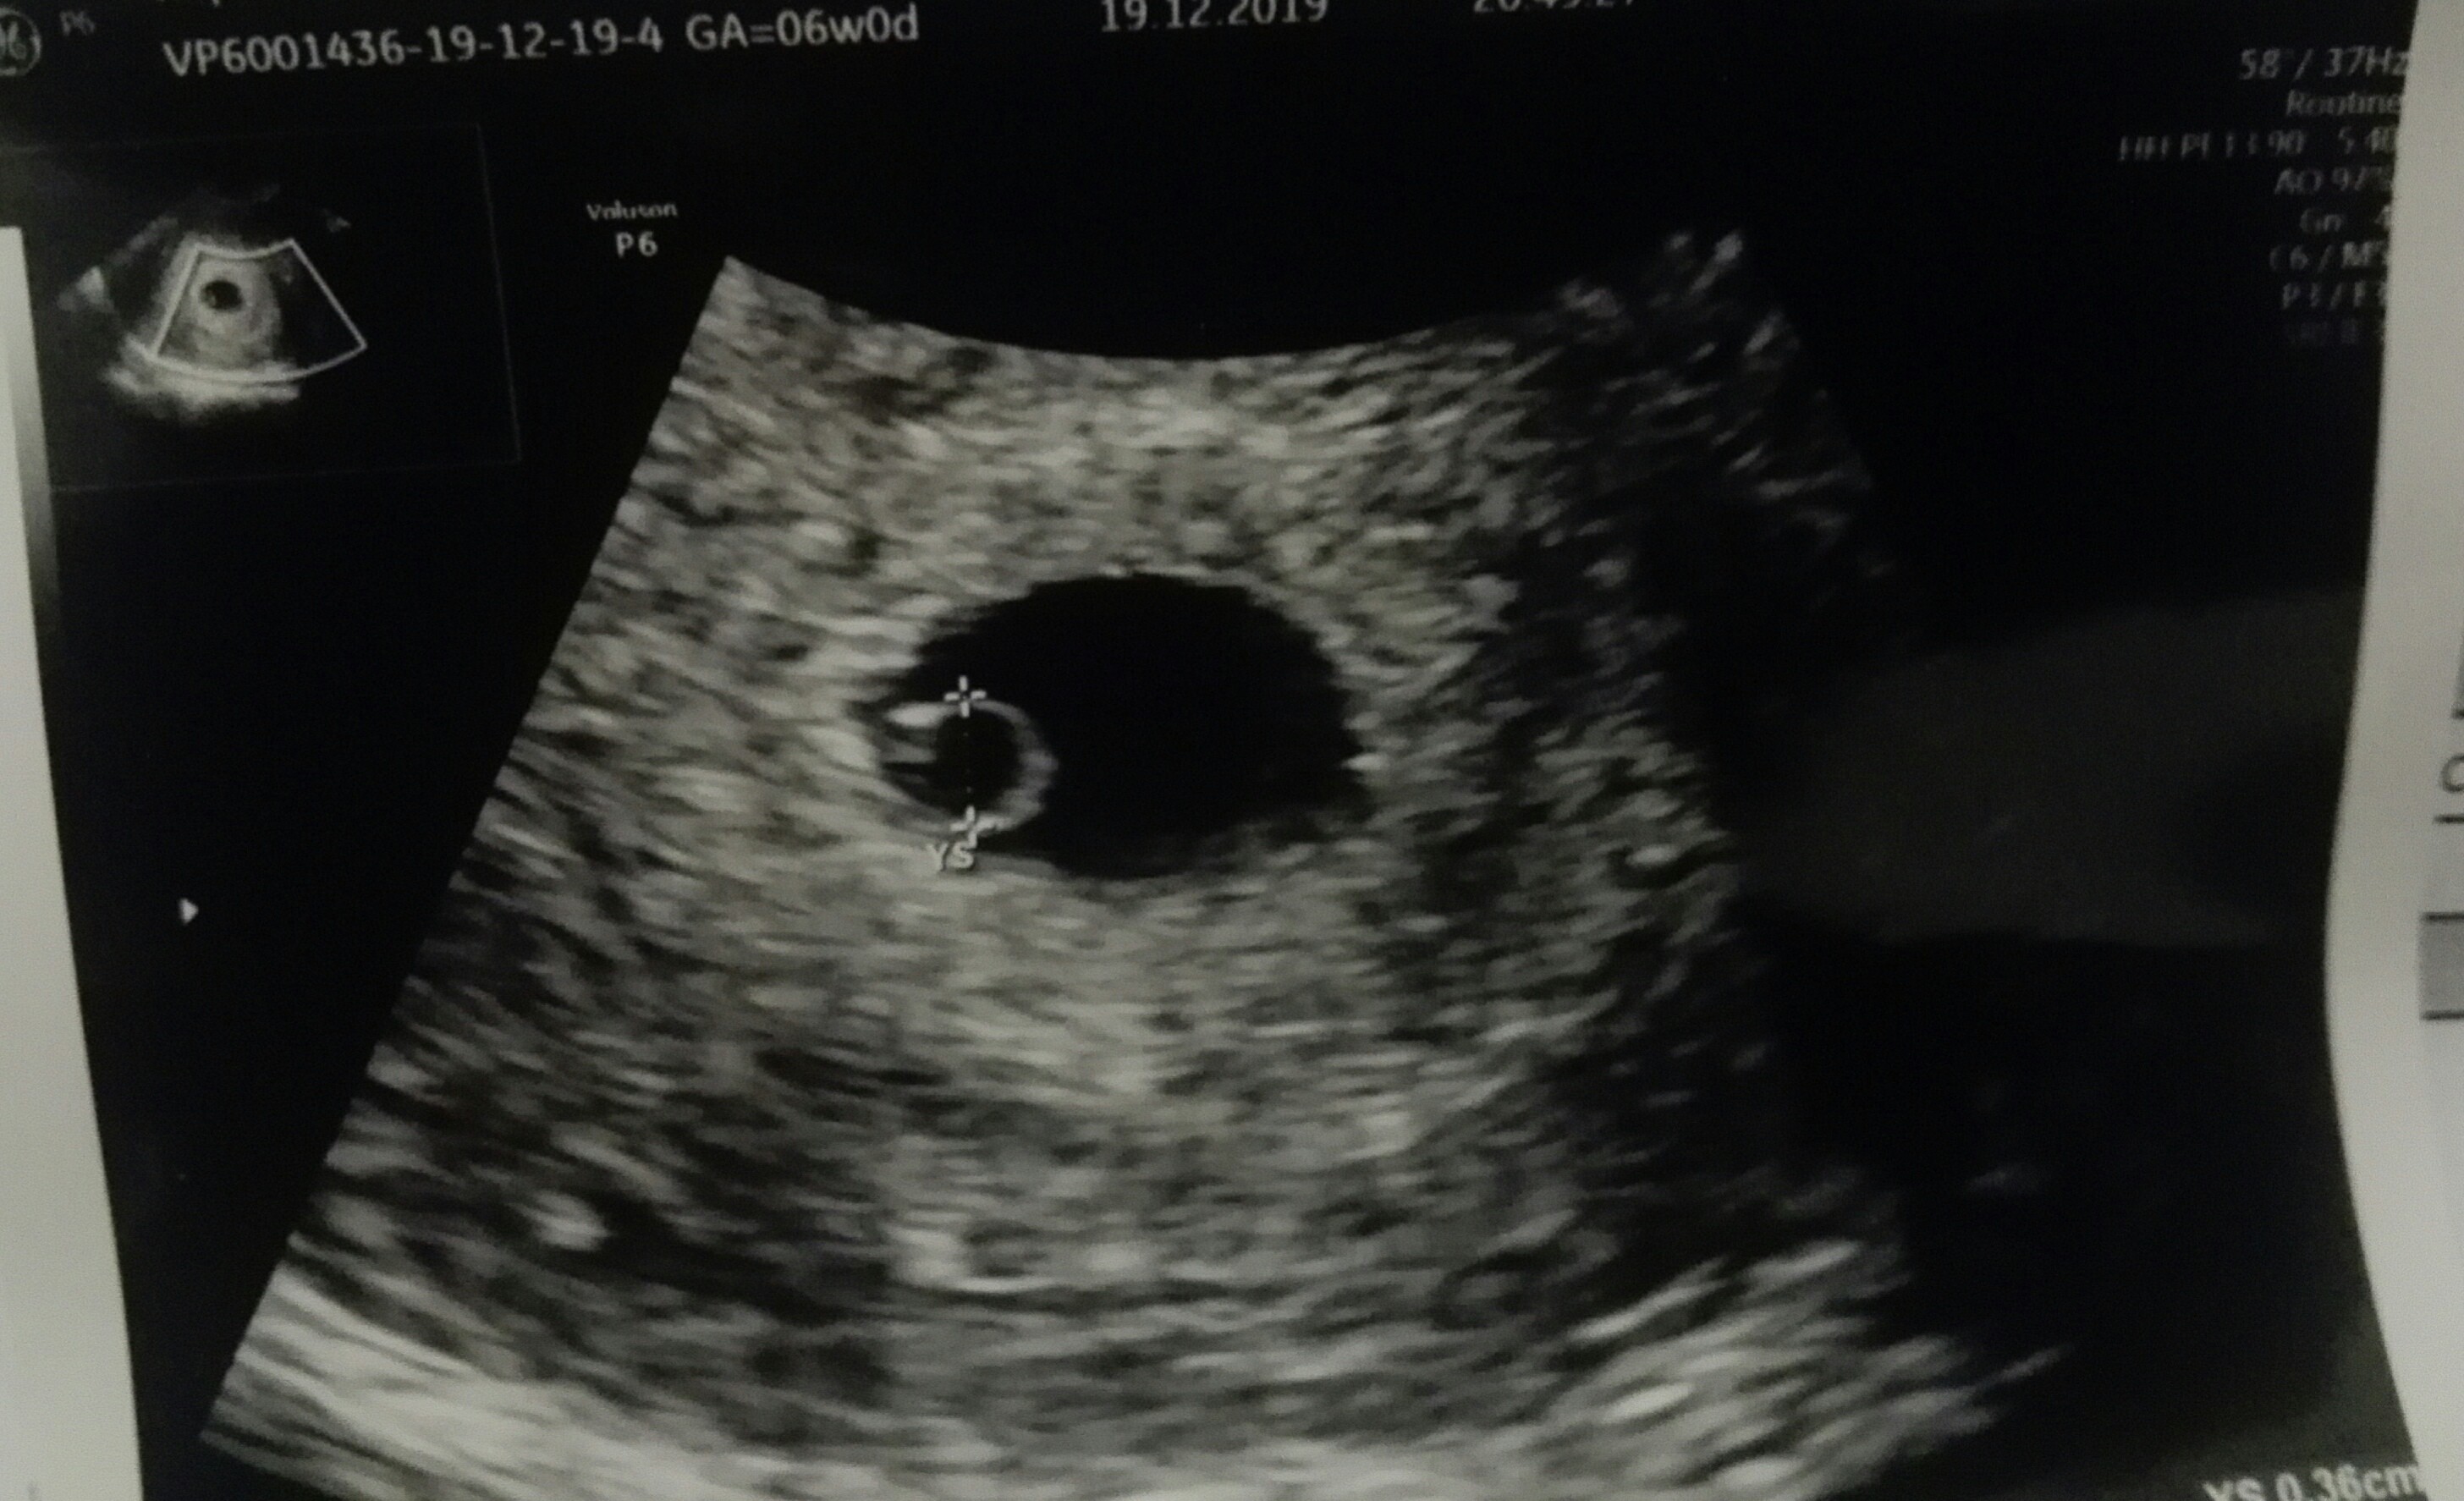

![]()